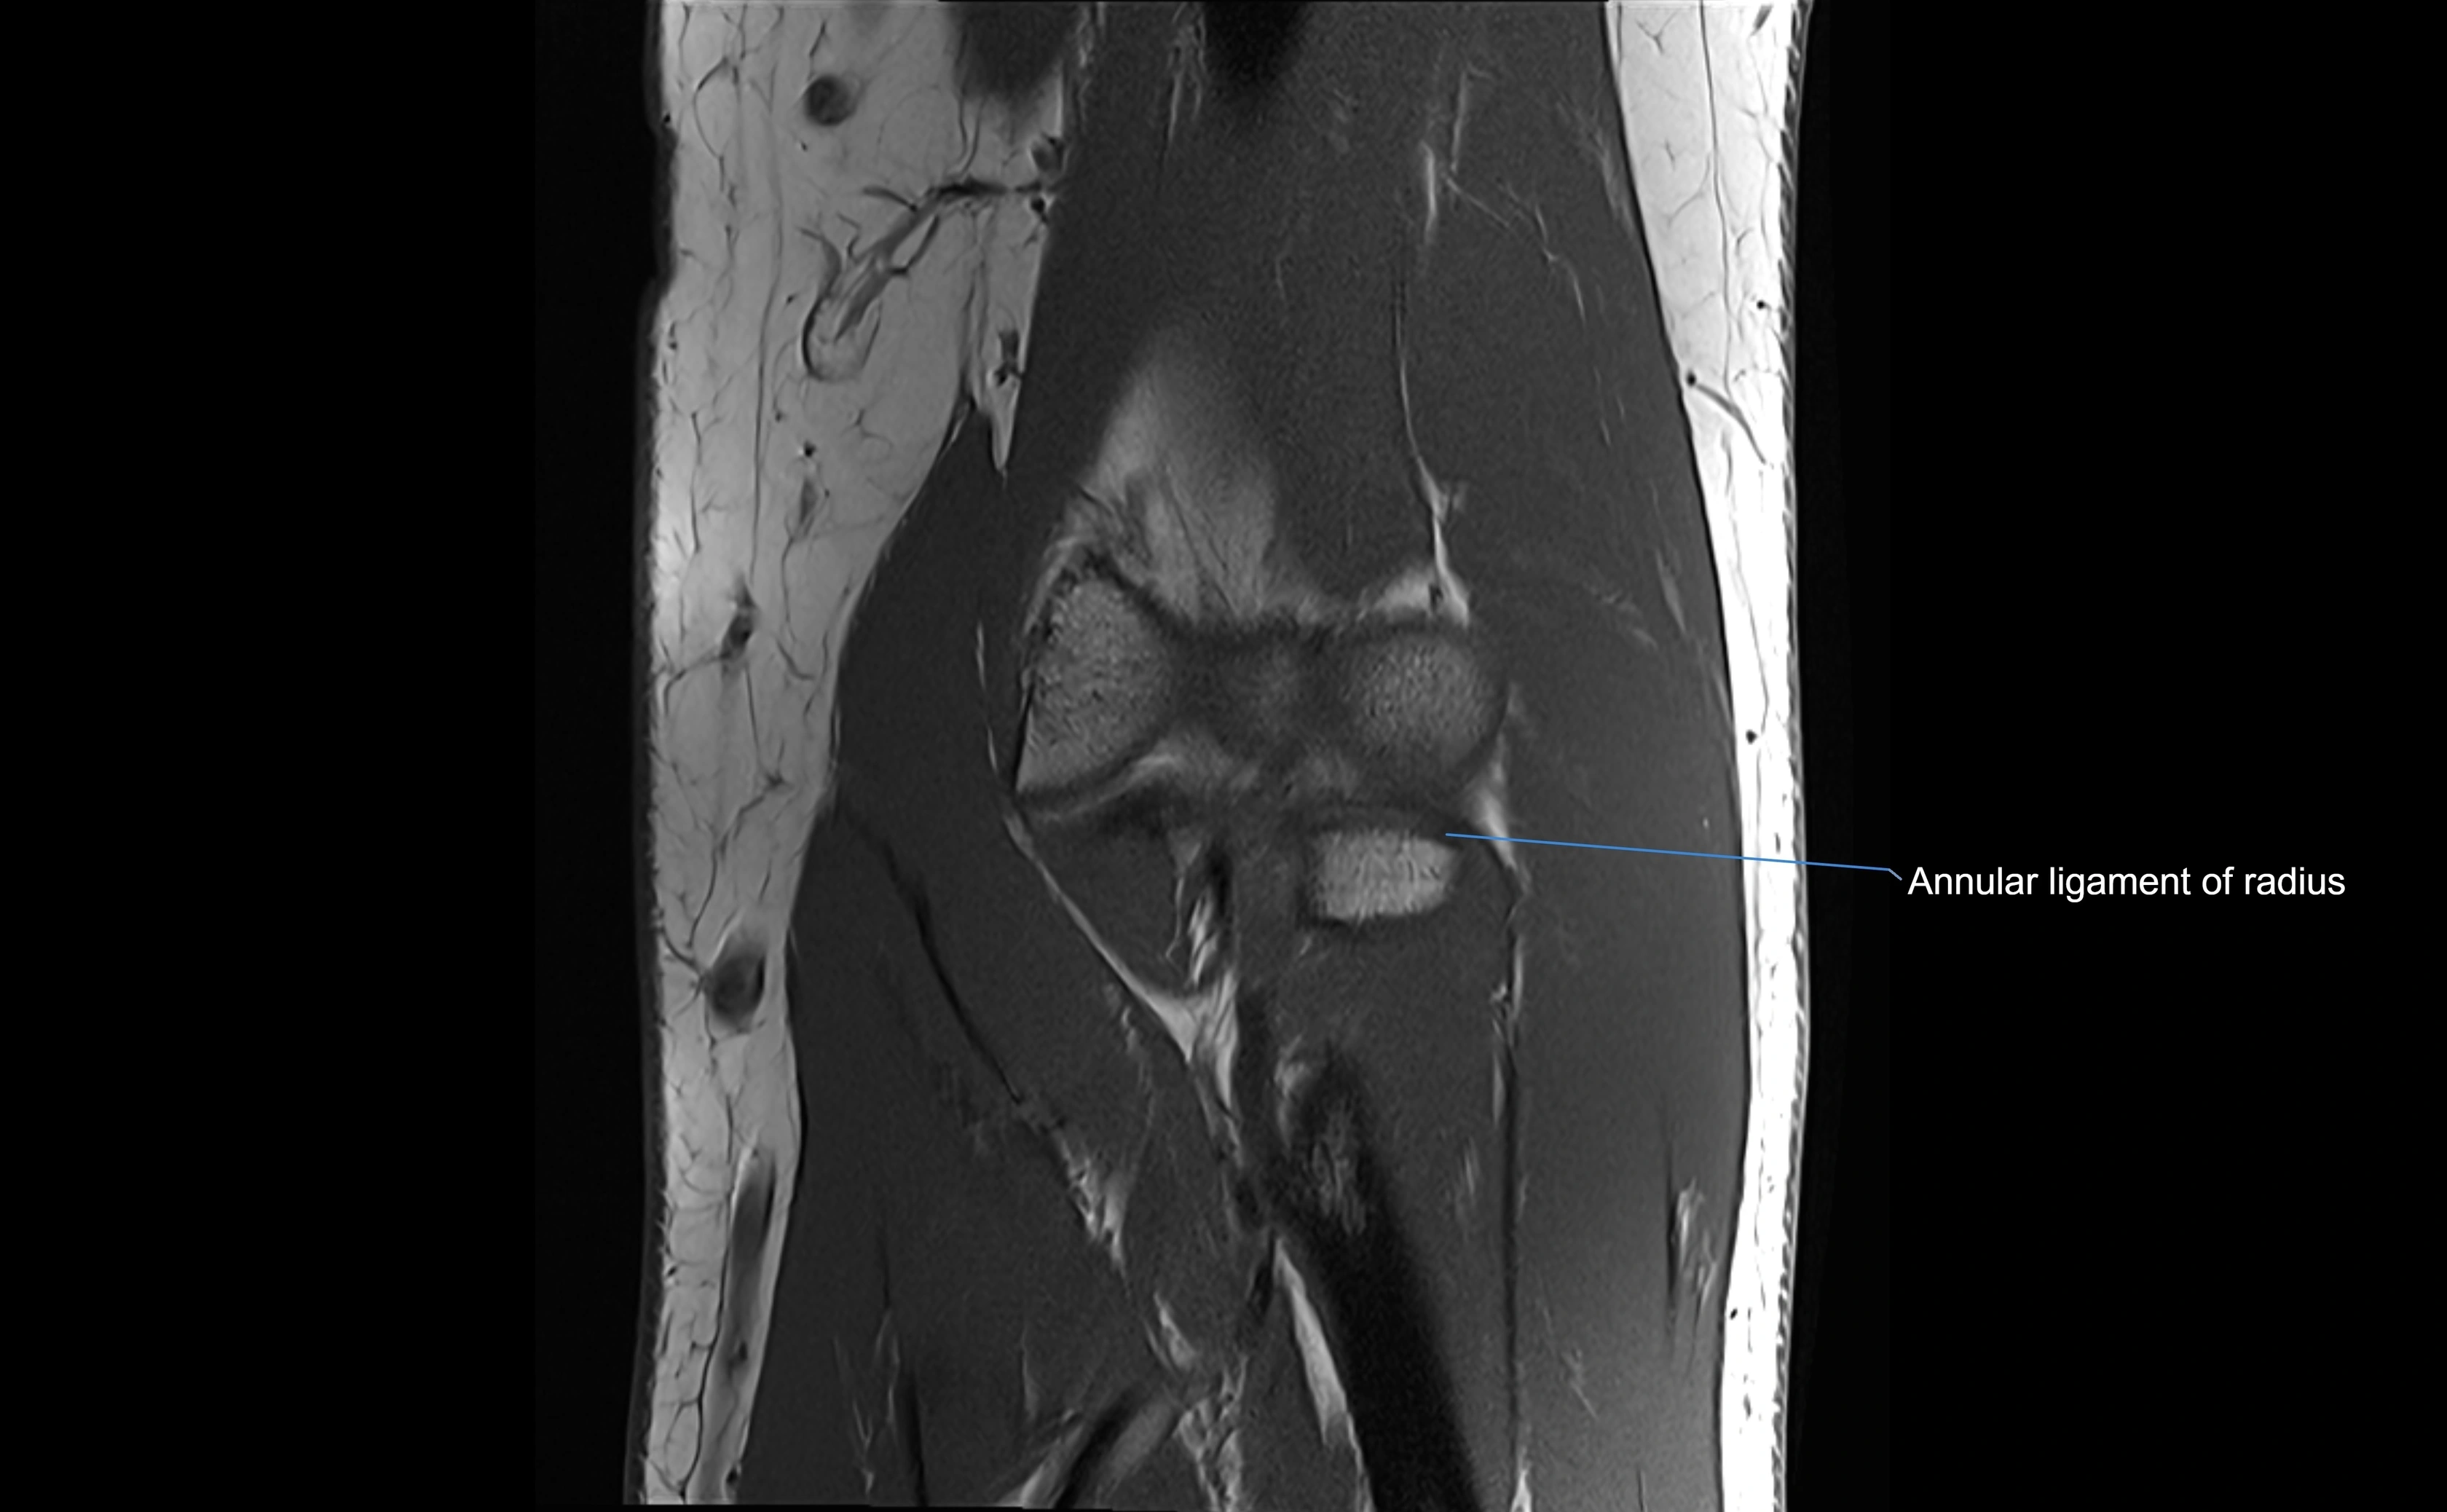

MRI images

image